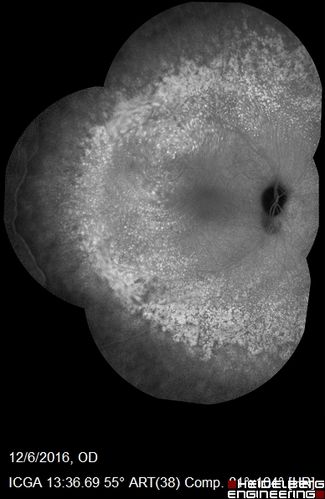

Ocular Lymphoma - non-Hodgkins - B-Cell

Multifocal sub-RPE lesions in the left eye of a patient with history of Non-hodgkins B-cell Lymphoma last active 2 years ago